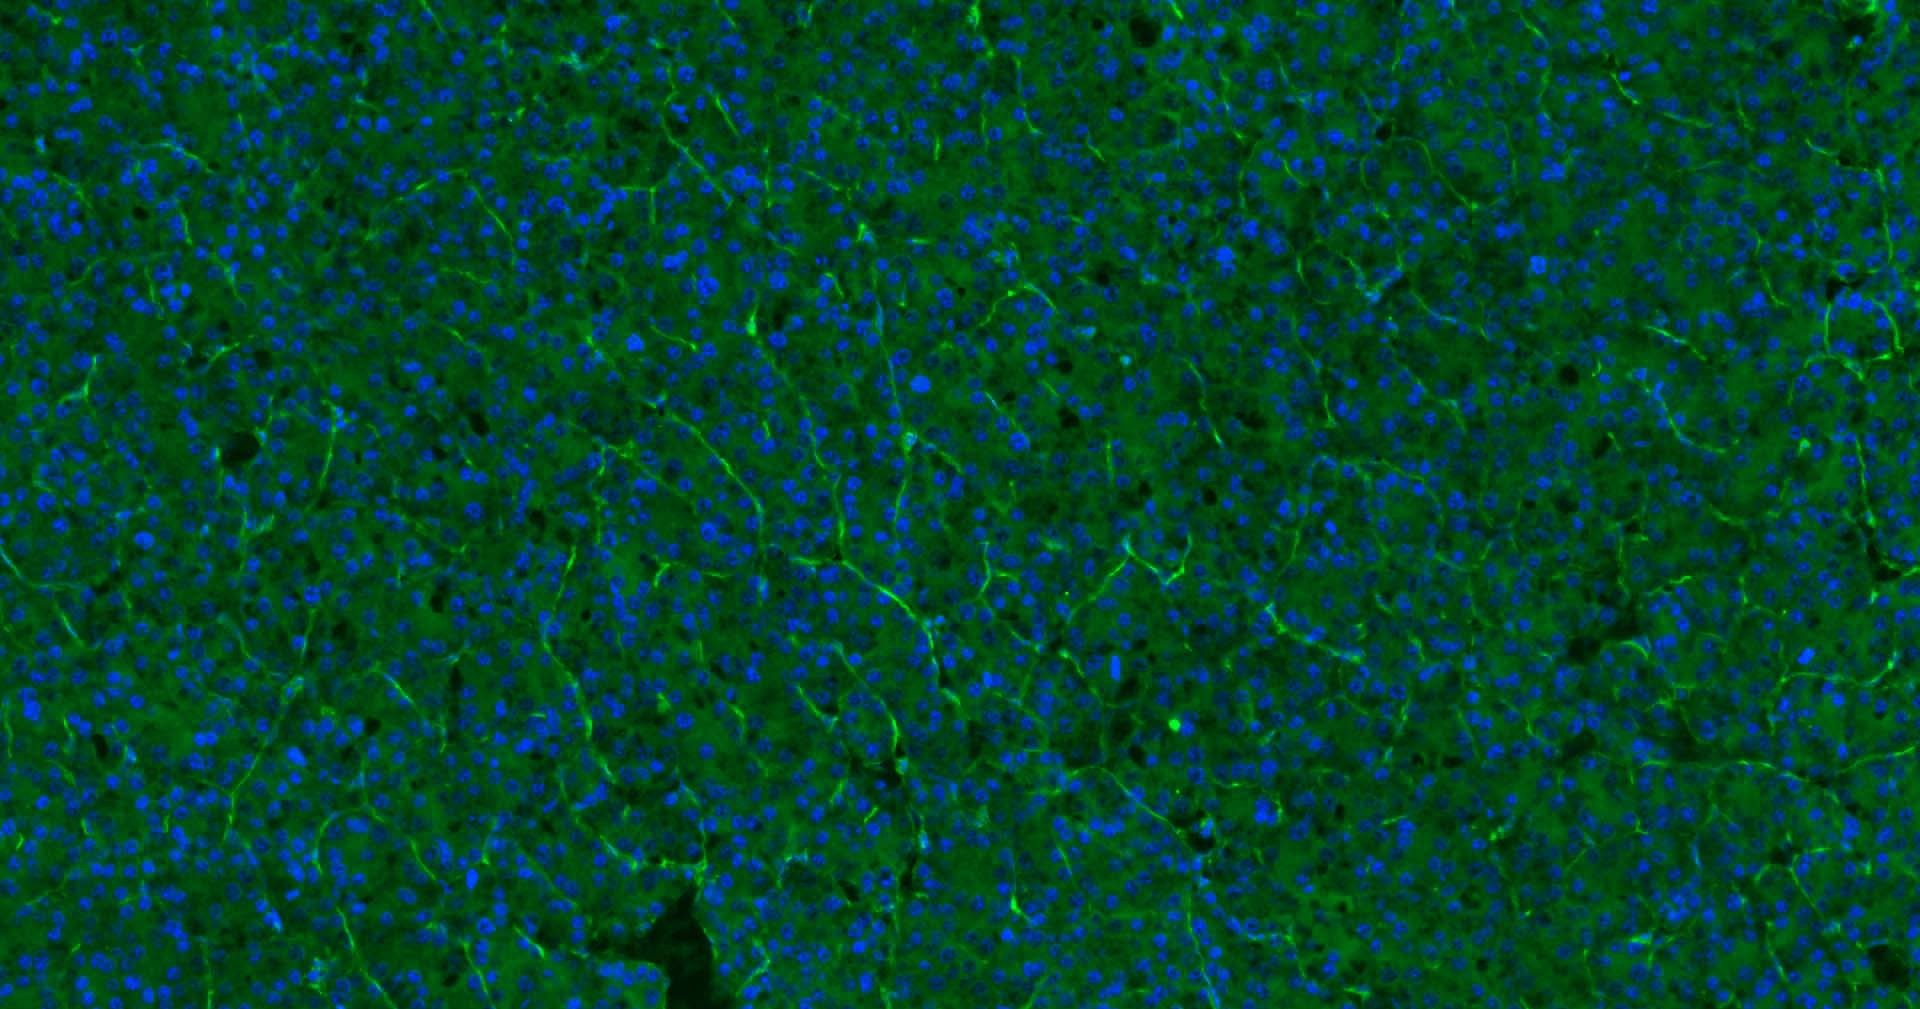

1. Paraformaldehyde-fixed, paraffin embedded Human Liver Cancer; Antigen retrieval by boiling in sodium citrate buffer (pH6.0) for 15 min; Antibody incubation with CD31 Monoclonal Antibody, Unconjugated (TMAB-00354) at 1:200 overnight at 4°C. Followed by conjugated Goat Anti-Rabbit IgG antibody (green), DAPI (blue) was used to stain the cell nucleus.

2. Paraformaldehyde-fixed, paraffin embedded Human Colon Cancer; Antigen retrieval by boiling in sodium citrate buffer (pH6.0) for 15 min; Antibody incubation with CD31 Monoclonal Antibody, Unconjugated (TMAB-00354) at 1:200 overnight at 4°C. Followed by conjugated Goat Anti-Rabbit IgG antibody (green), DAPI (blue) was used to stain the cell nucleus.